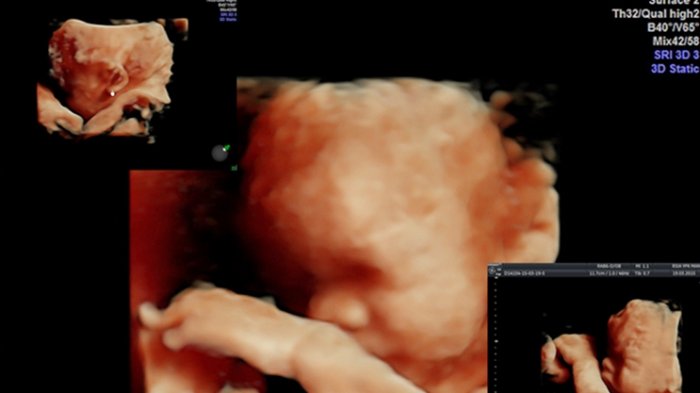

Kini, perkembangan USG tidak sekedar lagi gambar yang hitam dan putih (2D), melainkan telah adanya dimensi empat dimensi (4D).

Kehadiran 4D merupakan penyempurna dalam perkembangan teknologi ultrasonografi yang dapat merekam gerak janin di dalam rahim, meskipun demikian banyak juga yang mengatakan, bahwa ini merupakan USG live 3D atau dikatakan sebagai real time, hal ini berdasarkan dimensi yang ada hanya hingga 3D akan tetapi pemasar produk dalam mencuri konsumen memberikan nama USG 4D, lebih umum digunakan.

Pada dasarnya kemampuan USG 4D akan sama dengan kemampuan USG 3D yaitu membaca gerakan janin lebih akurat.

2. Mengetahui Gerakan Janin dengan Detail

Kelebihan yang dimiliki oleh USG 4D adalah mampu melihat gerakan janin seperti mampu menghisap ibu jari, memukul, menendang.

Dengan kemampuan ini akan memberikan informasi yang lebih banyak mengenai keadaan janin sehingga dapat mengamati perilaku janin.

Hal ini dapat membuat anda merasakan gerakan janin yang sesungguhnya seperti telah hadir di dunia.